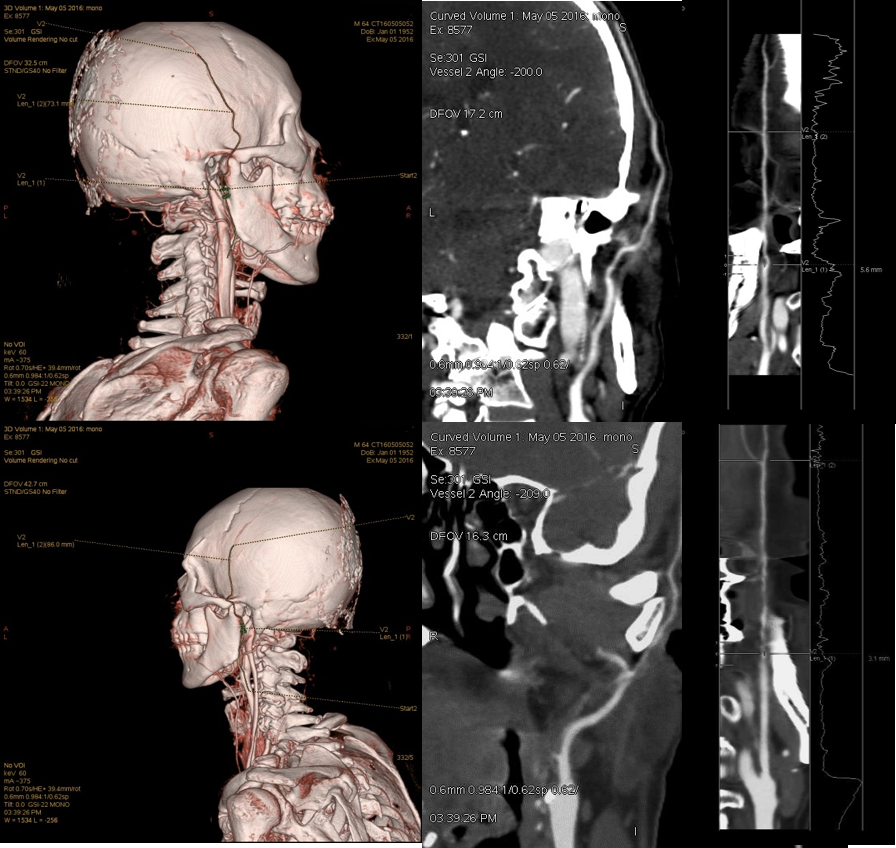

双侧颞浅血管状况及血管管径

双侧颞浅动脉在50keV显示清晰,远端分支良好。